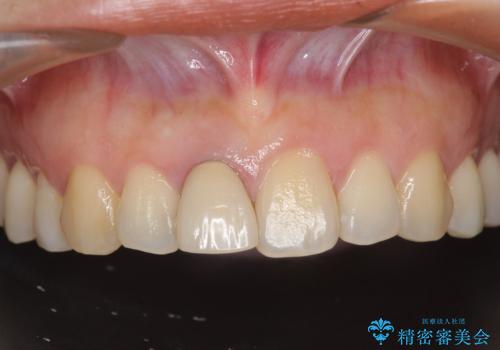

[ 前歯セラミック治療 ]白く不自然な前歯をきれいにしたい